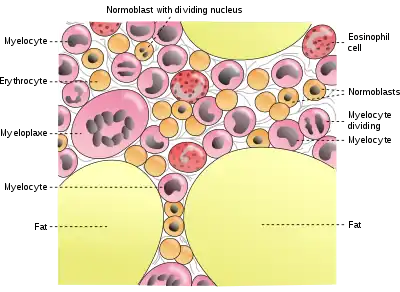

The cancellous part of bones contain bone marrow. Bone marrow produces blood cells in a process called hematopoiesis.[50] Blood cells that are created in bone marrow include red blood cells, platelets and white blood cells.[51] Progenitor cells such as the hematopoietic stem cell divide in a process called mitosis to produce precursor cells. These include precursors which eventually give rise to white blood cells, and erythroblasts which give rise to red blood cells.[52] Unlike red and white blood cells, created by mitosis, platelets are shed from very large cells called megakaryocytes.[53] This process of progressive differentiation occurs within the bone marrow. After the cells are matured, they enter the circulation.[54] Every day, over 2.5 billion red blood cells and platelets, and 50–100 billion granulocytes are produced in this way.[22]

As well as creating cells, bone marrow is also one of the major sites where defective or aged red blood cells are destroyed.[22]

Cells in bone marrow